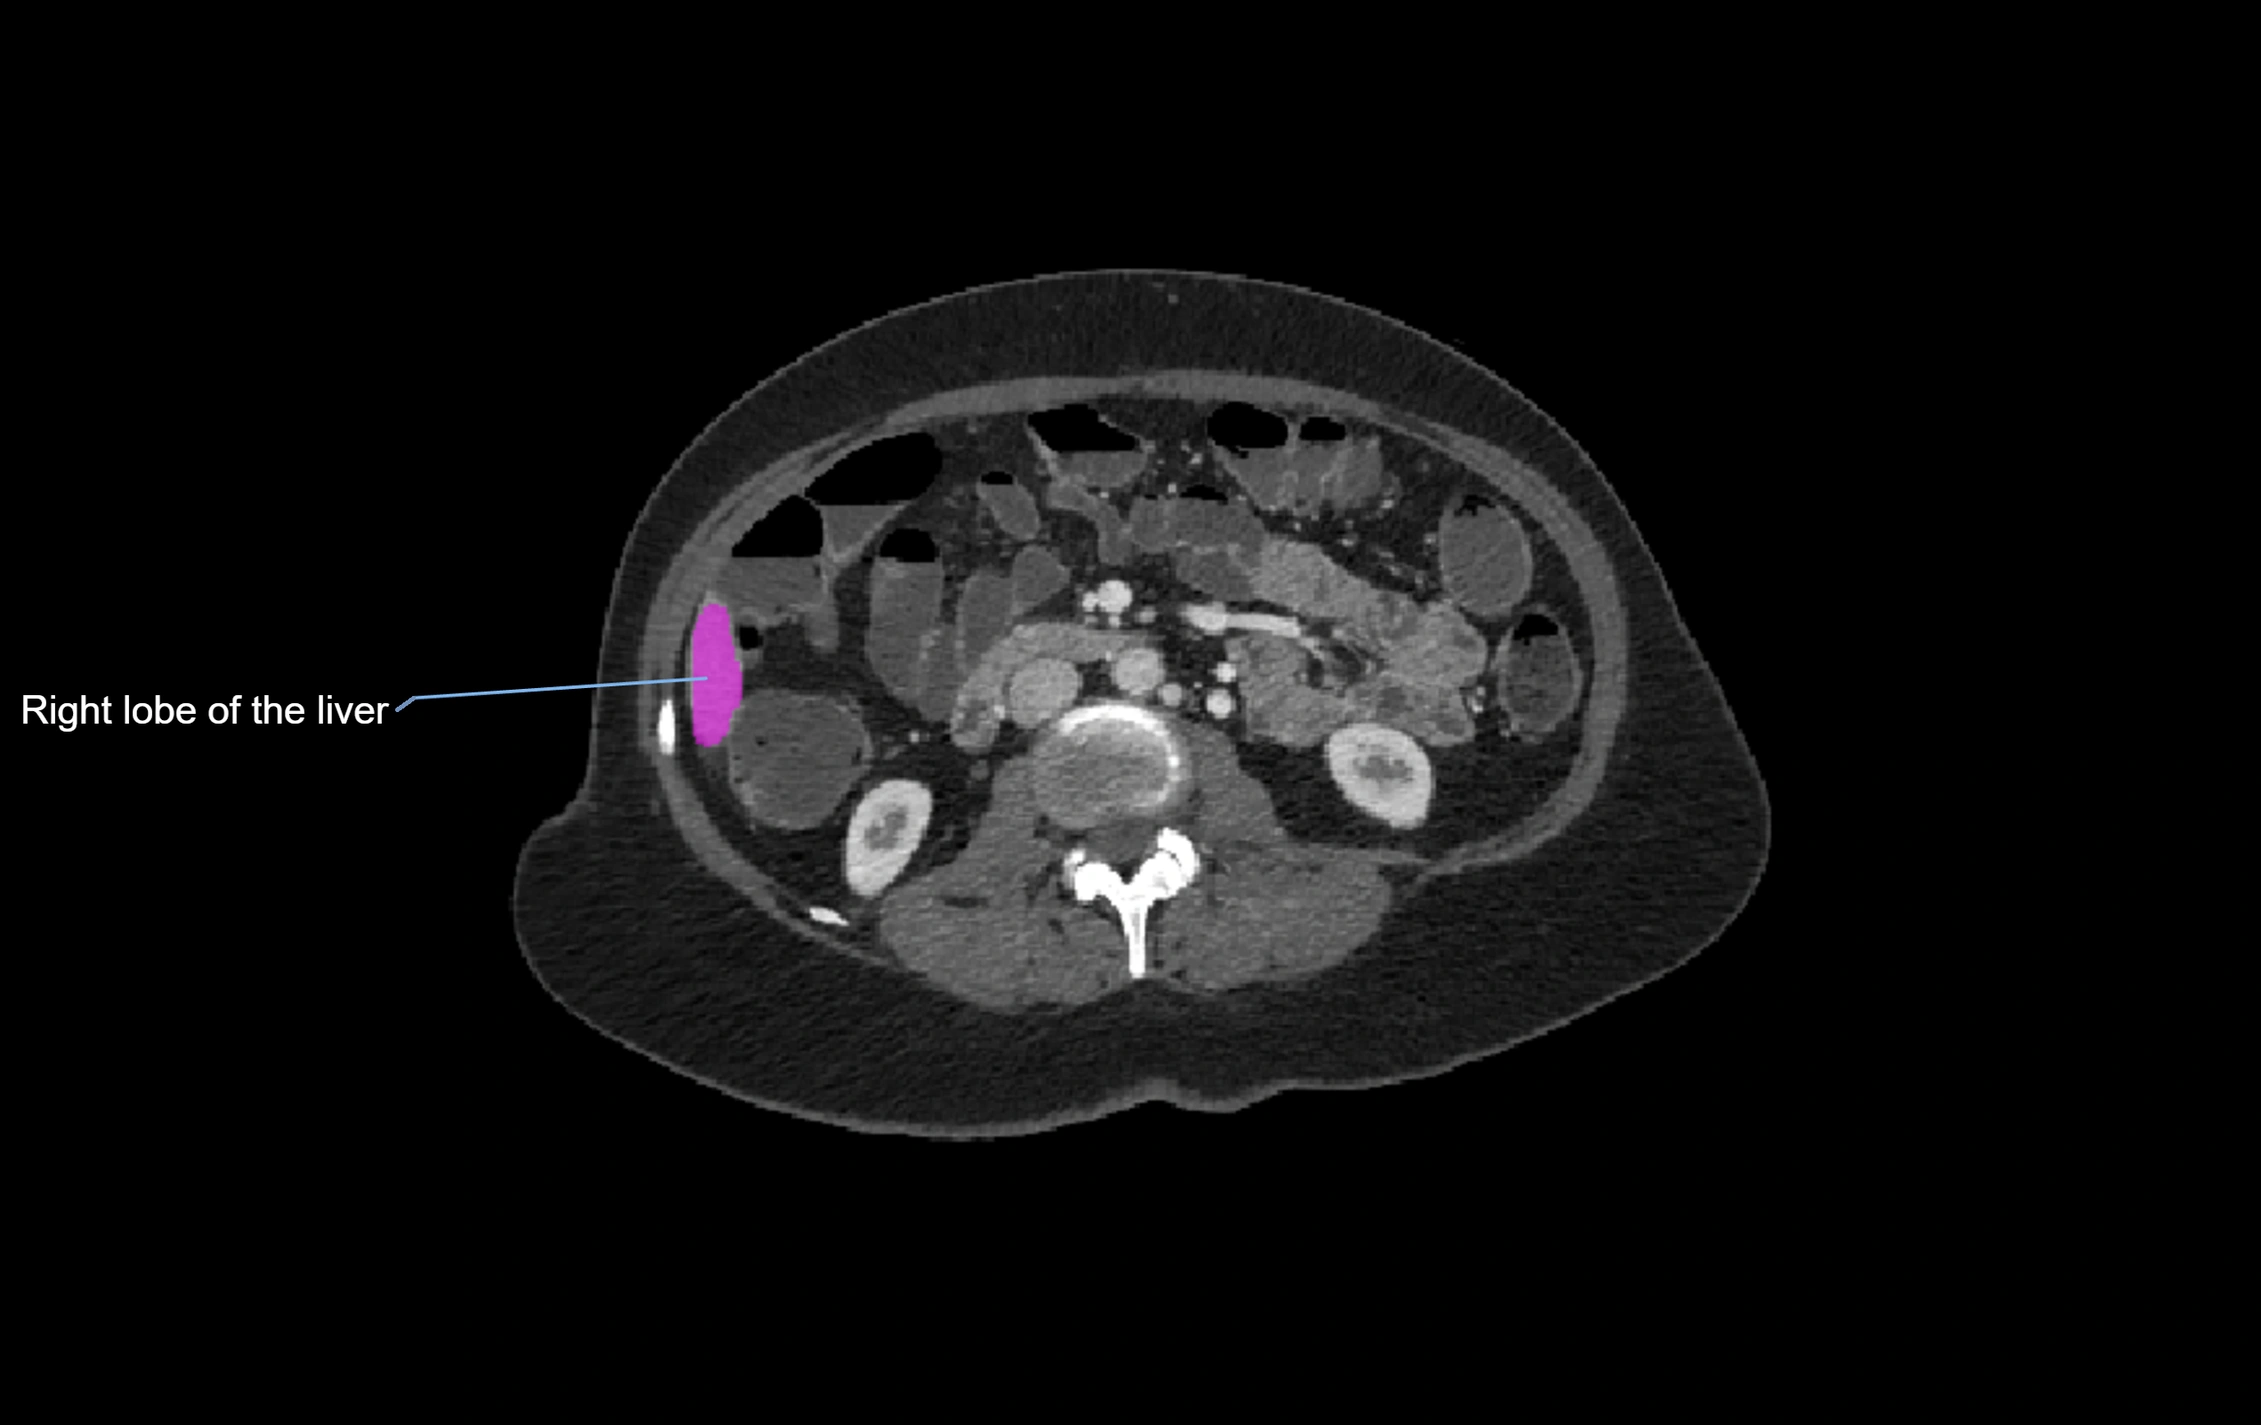

CT Image

image